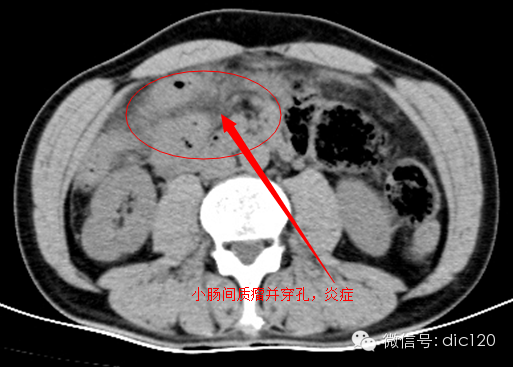

3,炎症

典型的小肠系膜炎症浸润可见于胰腺炎,重型胰腺炎时,释放的胰酶渗入小网膜内或沿身旁前间隙进入小肠系膜,有时甚至结肠系膜。其他局灶性炎症如阑尾炎、炎性肠病及憩室炎也可引起附近小肠系膜的炎症。腹部结核最常表现为淋巴结结核,尽管受累淋巴结直径可达3公分,但多数只是表现淋巴结数量增多,大小仍正常,肠系膜可弥漫浸润,肠攀粘连,肠系膜表面有小结节,大网膜浸润,肠壁受侵,淋巴结边缘强化而中养成低密度